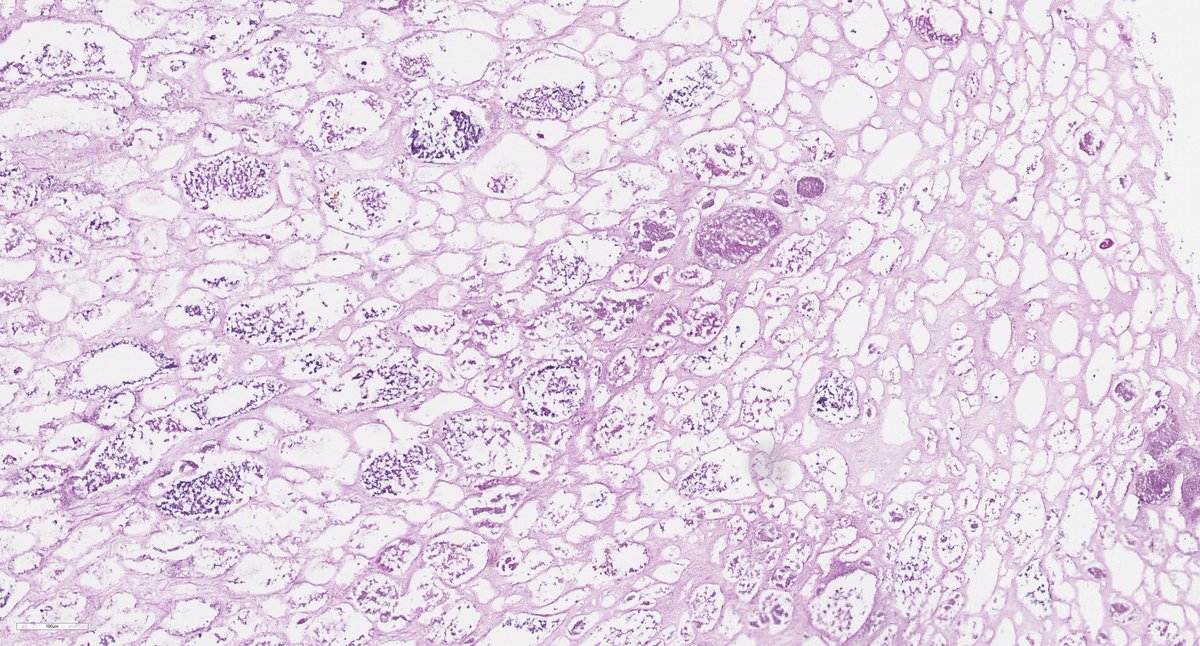

Disappearing glomeruli: loss of linear IgG in anti-GBM nephritis